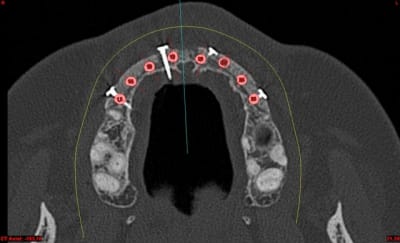

Dar axial lebnbu - Eugenol

Dar axiali qui1is - Eugenol

Dar11 cyo3el - Eugenol

Dar13 alznrp - Eugenol

Dar13i aujibg - Eugenol

Dar14 actm24 - Eugenol

Dar15 zvi82y - Eugenol

Dar23i g6nxds - Eugenol

Dar24 vzfroa - Eugenol

Dar25 lcptyk - Eugenol

Dar 3d xkb3uv - Eugenol

Dar  3di ngfcc4 - Eugenol

Dar  3dl fwmdk6 - Eugenol

Céramik

image 8, il semble y avoir une zone entre le greffon et l'os ?

C'est intégré ?